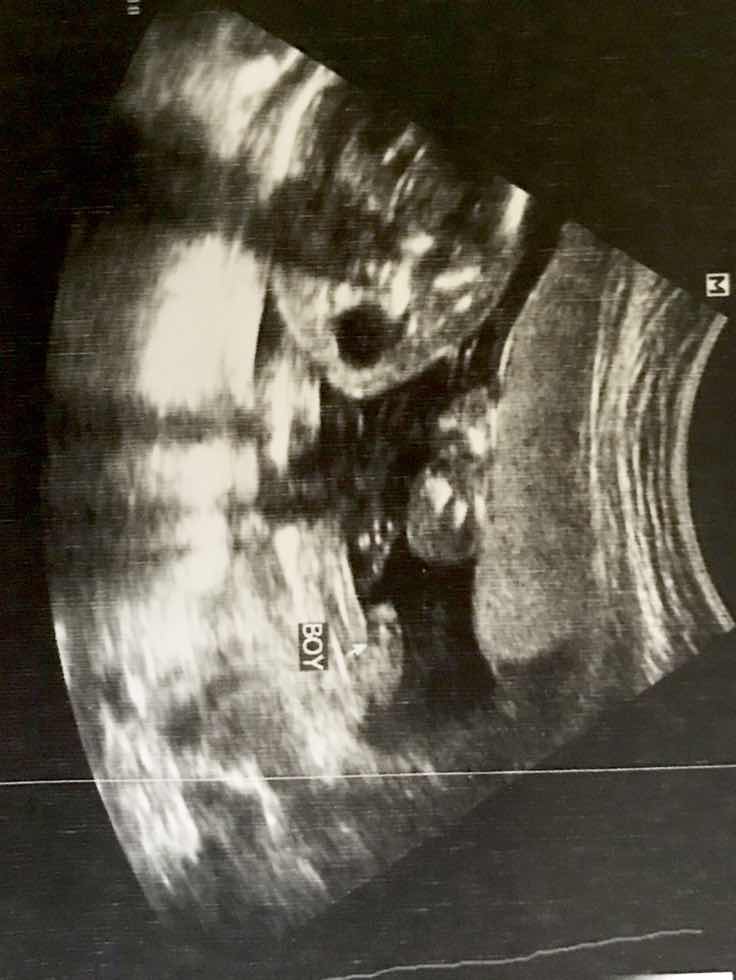

Hi mga momsh tanung ko lang db accurate naman na boy ang baby ko kahit 23 weeks plng ako CAS kahapon, may lawit, eh meron nagsasabi pag 5months hindi pa sure gender,? Db boy po yan. Salamat #FTM

Boy po tsaka CAS napo eh kaya sure na.